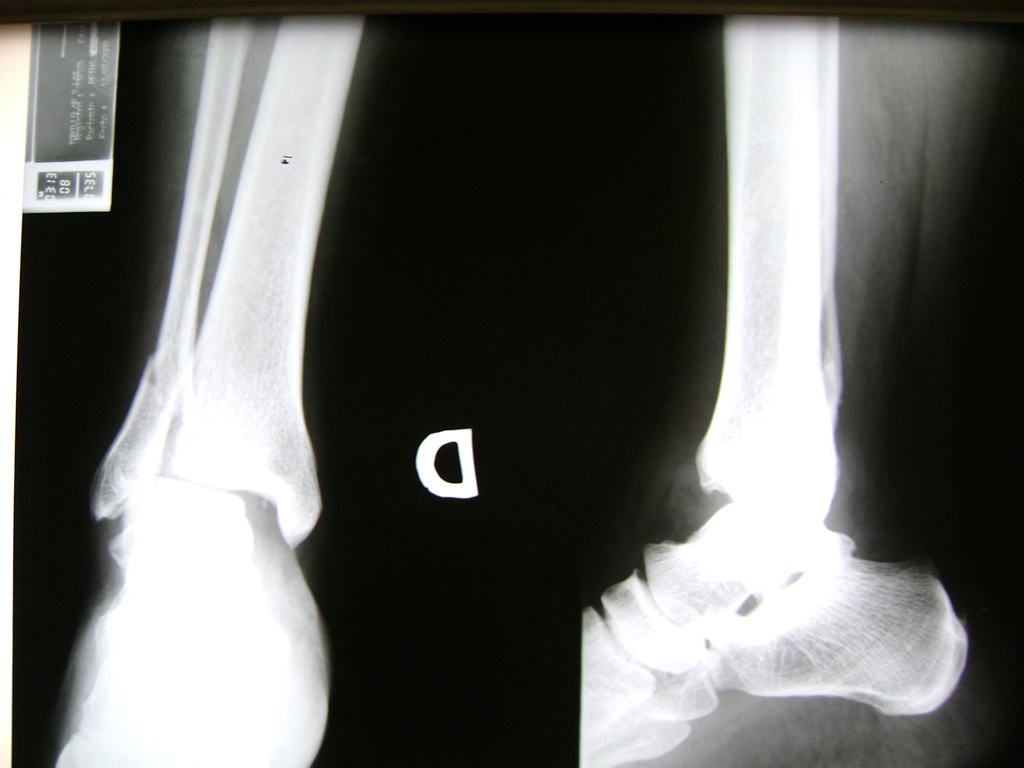

Una fractura de tobillo es la rotura de uno o más de los huesos del tobillo. Estas fracturas pueden ser:

Algunas fracturas de tobillo pueden requerir cirugía si:

- Los extremos de los huesos están desalineados entre sí (desplazados).

- La fractura se extiende hasta la articulación del tobillo (fractura intra-articular).

- Los tendones o ligamentos (tejidos que sujetan los músculos y los huesos entre sí) están rotos.

- El médico cree que sus huesos probablemente no sanen apropiadamente sin cirugía.

- El médico considera que la cirugía puede permitirle una recuperación más rápida y confiable.

- En los niños, la fractura involucra la parte del hueso del tobillo donde el hueso está creciendo.

Cuando se necesita cirugía, es probable que esta implique el uso de clavijas de metal, tornillos o placas para sostener los huesos en su lugar mientras la fractura se consolida. Los elementos de soporte pueden ser temporales o permanentes.